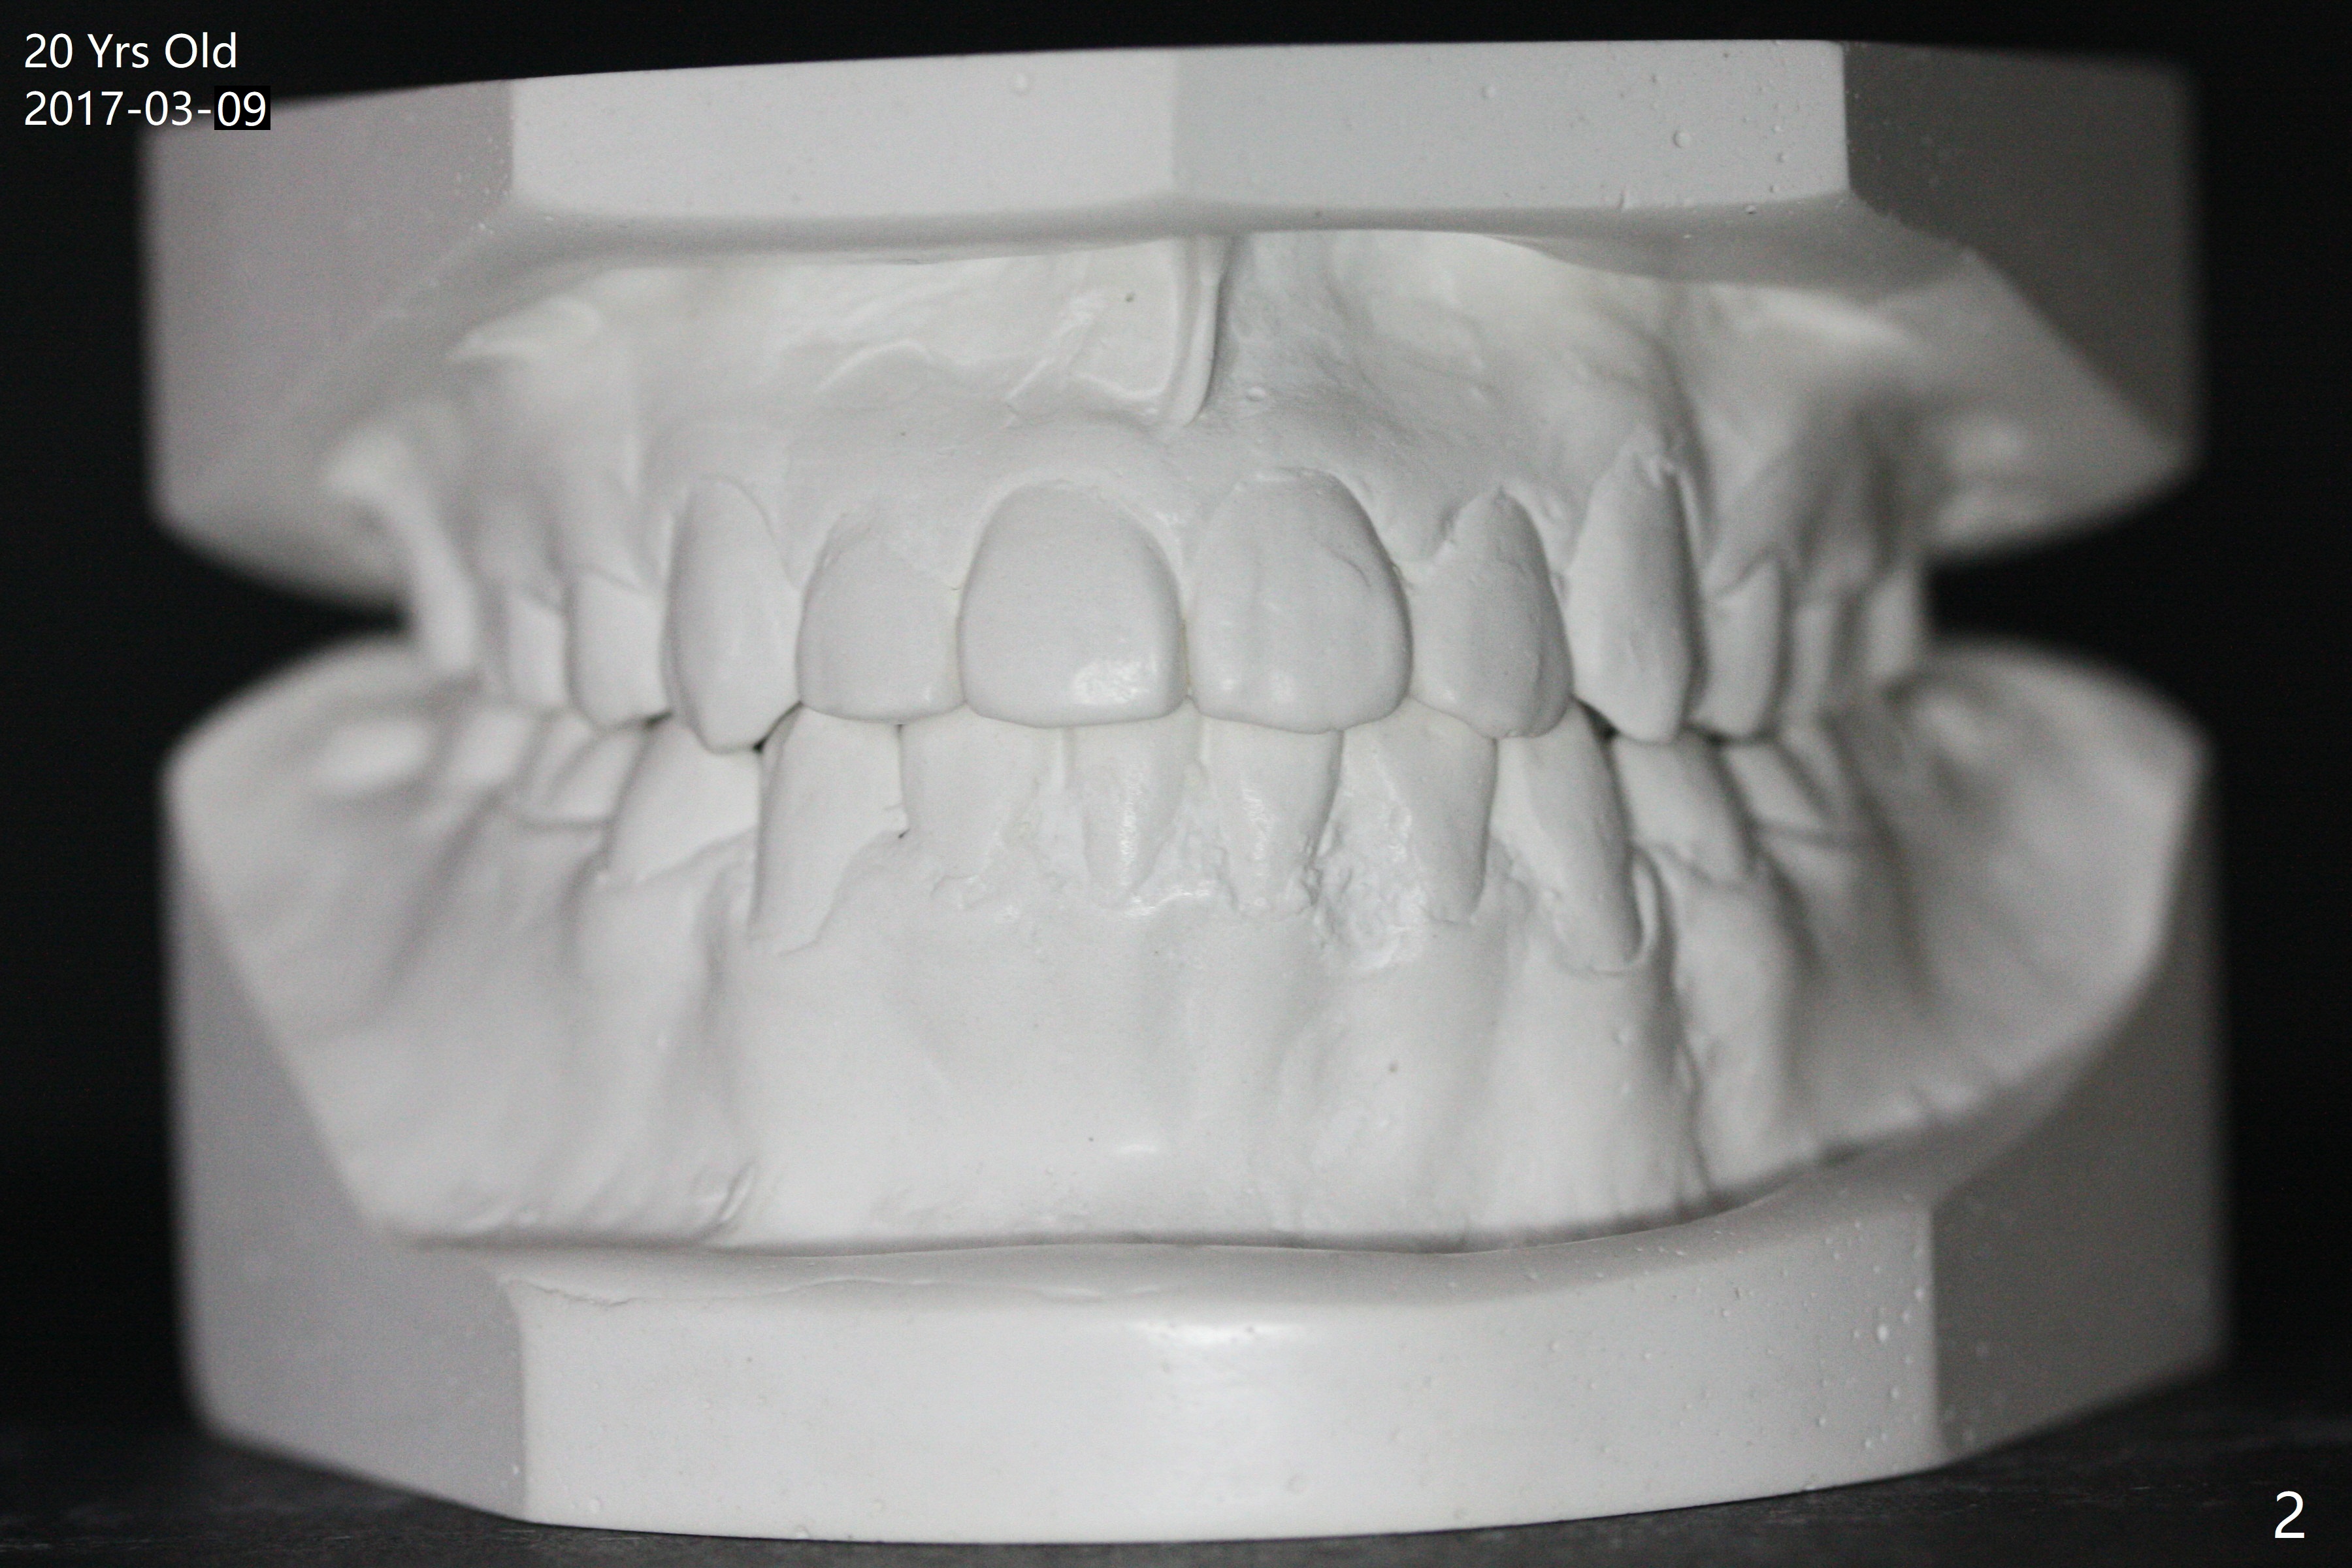

A 16-year-old man has severe crowding, but the open bite is ignored (Fig.1,4,7,10,13). The orthodontic treatment lasts 4 years 5 months, including failure to return for a period of time. The open bite seems to have been corrected (Fig.2, 5, 8, 11, 14). Suction down retainers are provided. In less than 2 years, the patient returns requesting remaking retainers. It appears that open bite relapses (Fig.3,6,9,12,15), as related to supraeruption of the lower 2nd molars (Fig.6,9 arrows). The latter is apparently associated with the erupting 3rd molars.